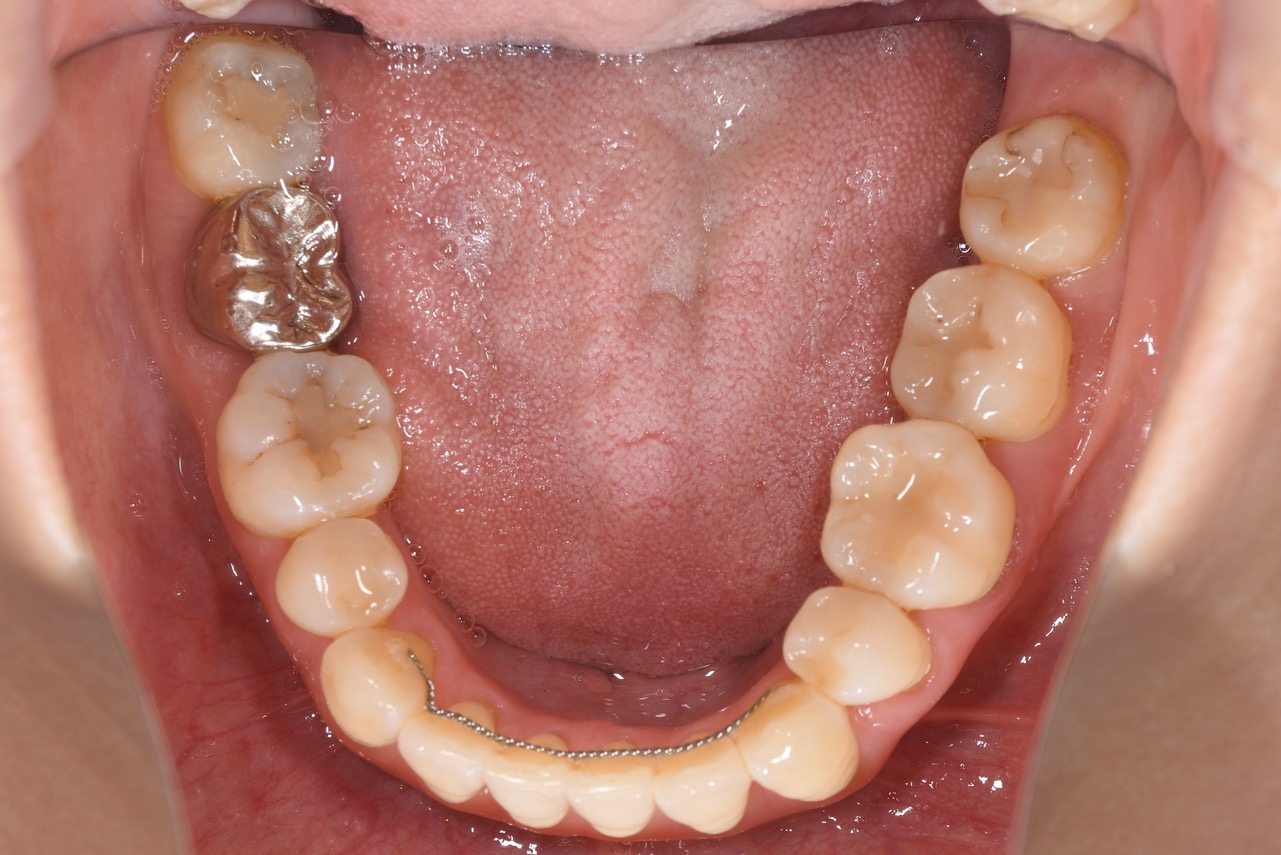

まず、視診や問診を行い、お口の中全体の状態を把握します。患者さんのおっしゃる通り、見た目には大きな虫歯や歯の破折などは認められませんでした。しかし、レントゲン撮影を行ったところ、問題の原因が明確になりました。

レントゲン写真には、問題の歯の根の先端(根尖)を取り囲むように、黒い影がはっきりと写っていました。これは根尖病変(こんせんびょうへん)と呼ばれるもので、歯の根の先に膿の袋ができて骨を溶かしている状態です。

患者さんの場合、この根尖病変がかなり大きくなっており、歯茎にはフィステル(瘻孔:ろうこう)も認められました。これが、噛んだ時の違和感の原因でした。他院で抜歯と診断されたのも、この病変の大きさが理由だと考えられます。